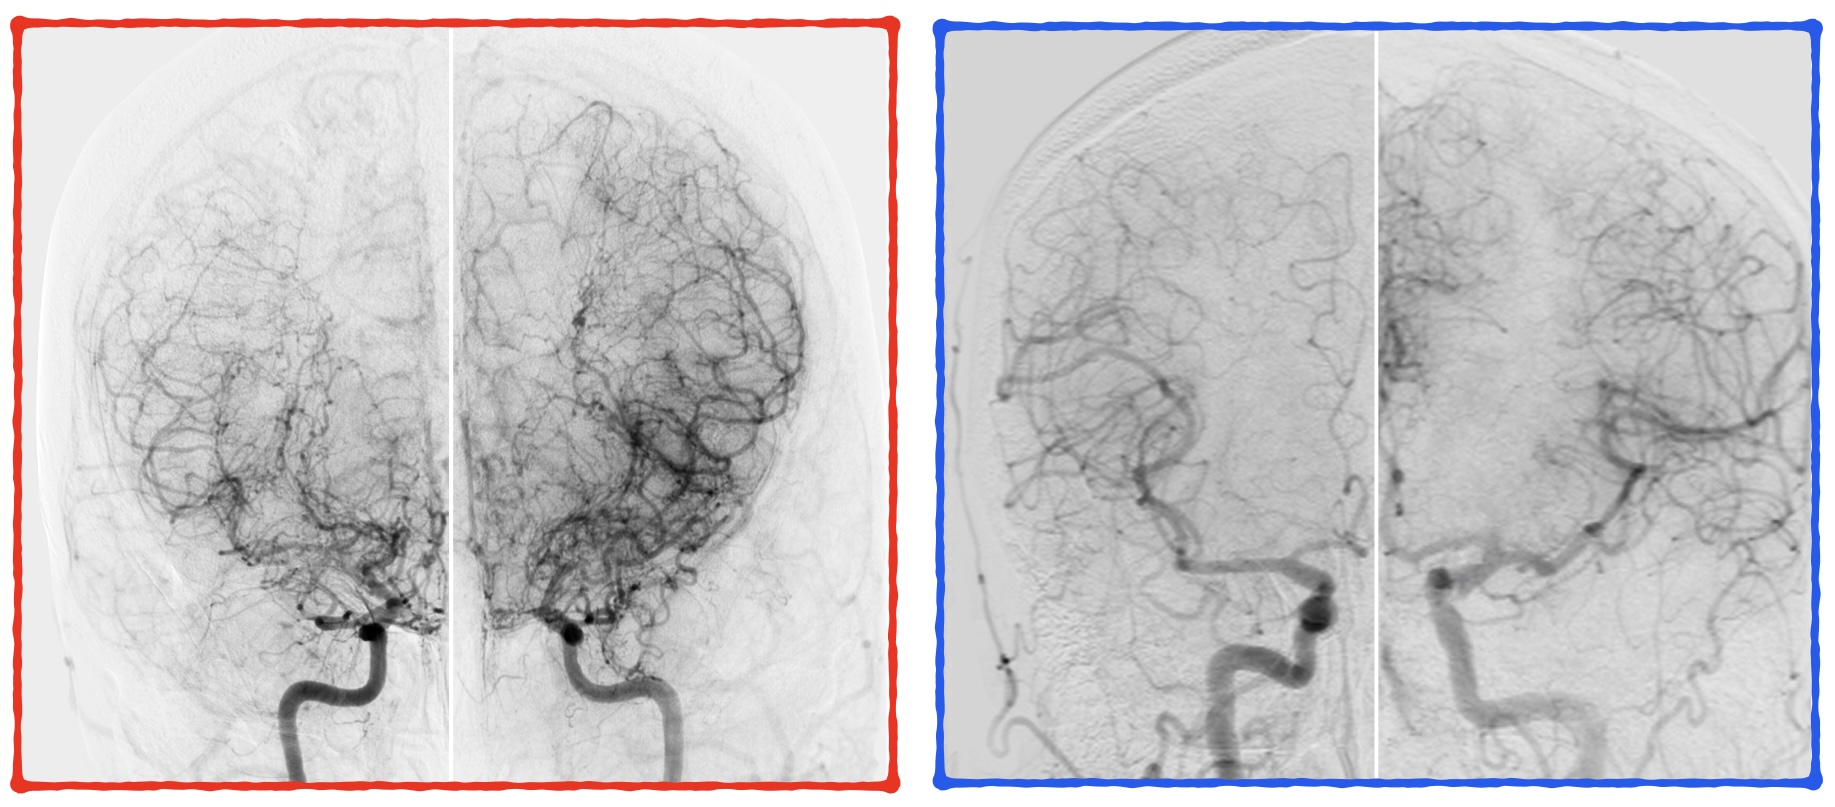

MAV – Malformação Arteriovenosa

Avaliação completa e tratamento de malformações arteriovenosas, utilizando abordagens que visam reduzir riscos e preservar a função neurológica.